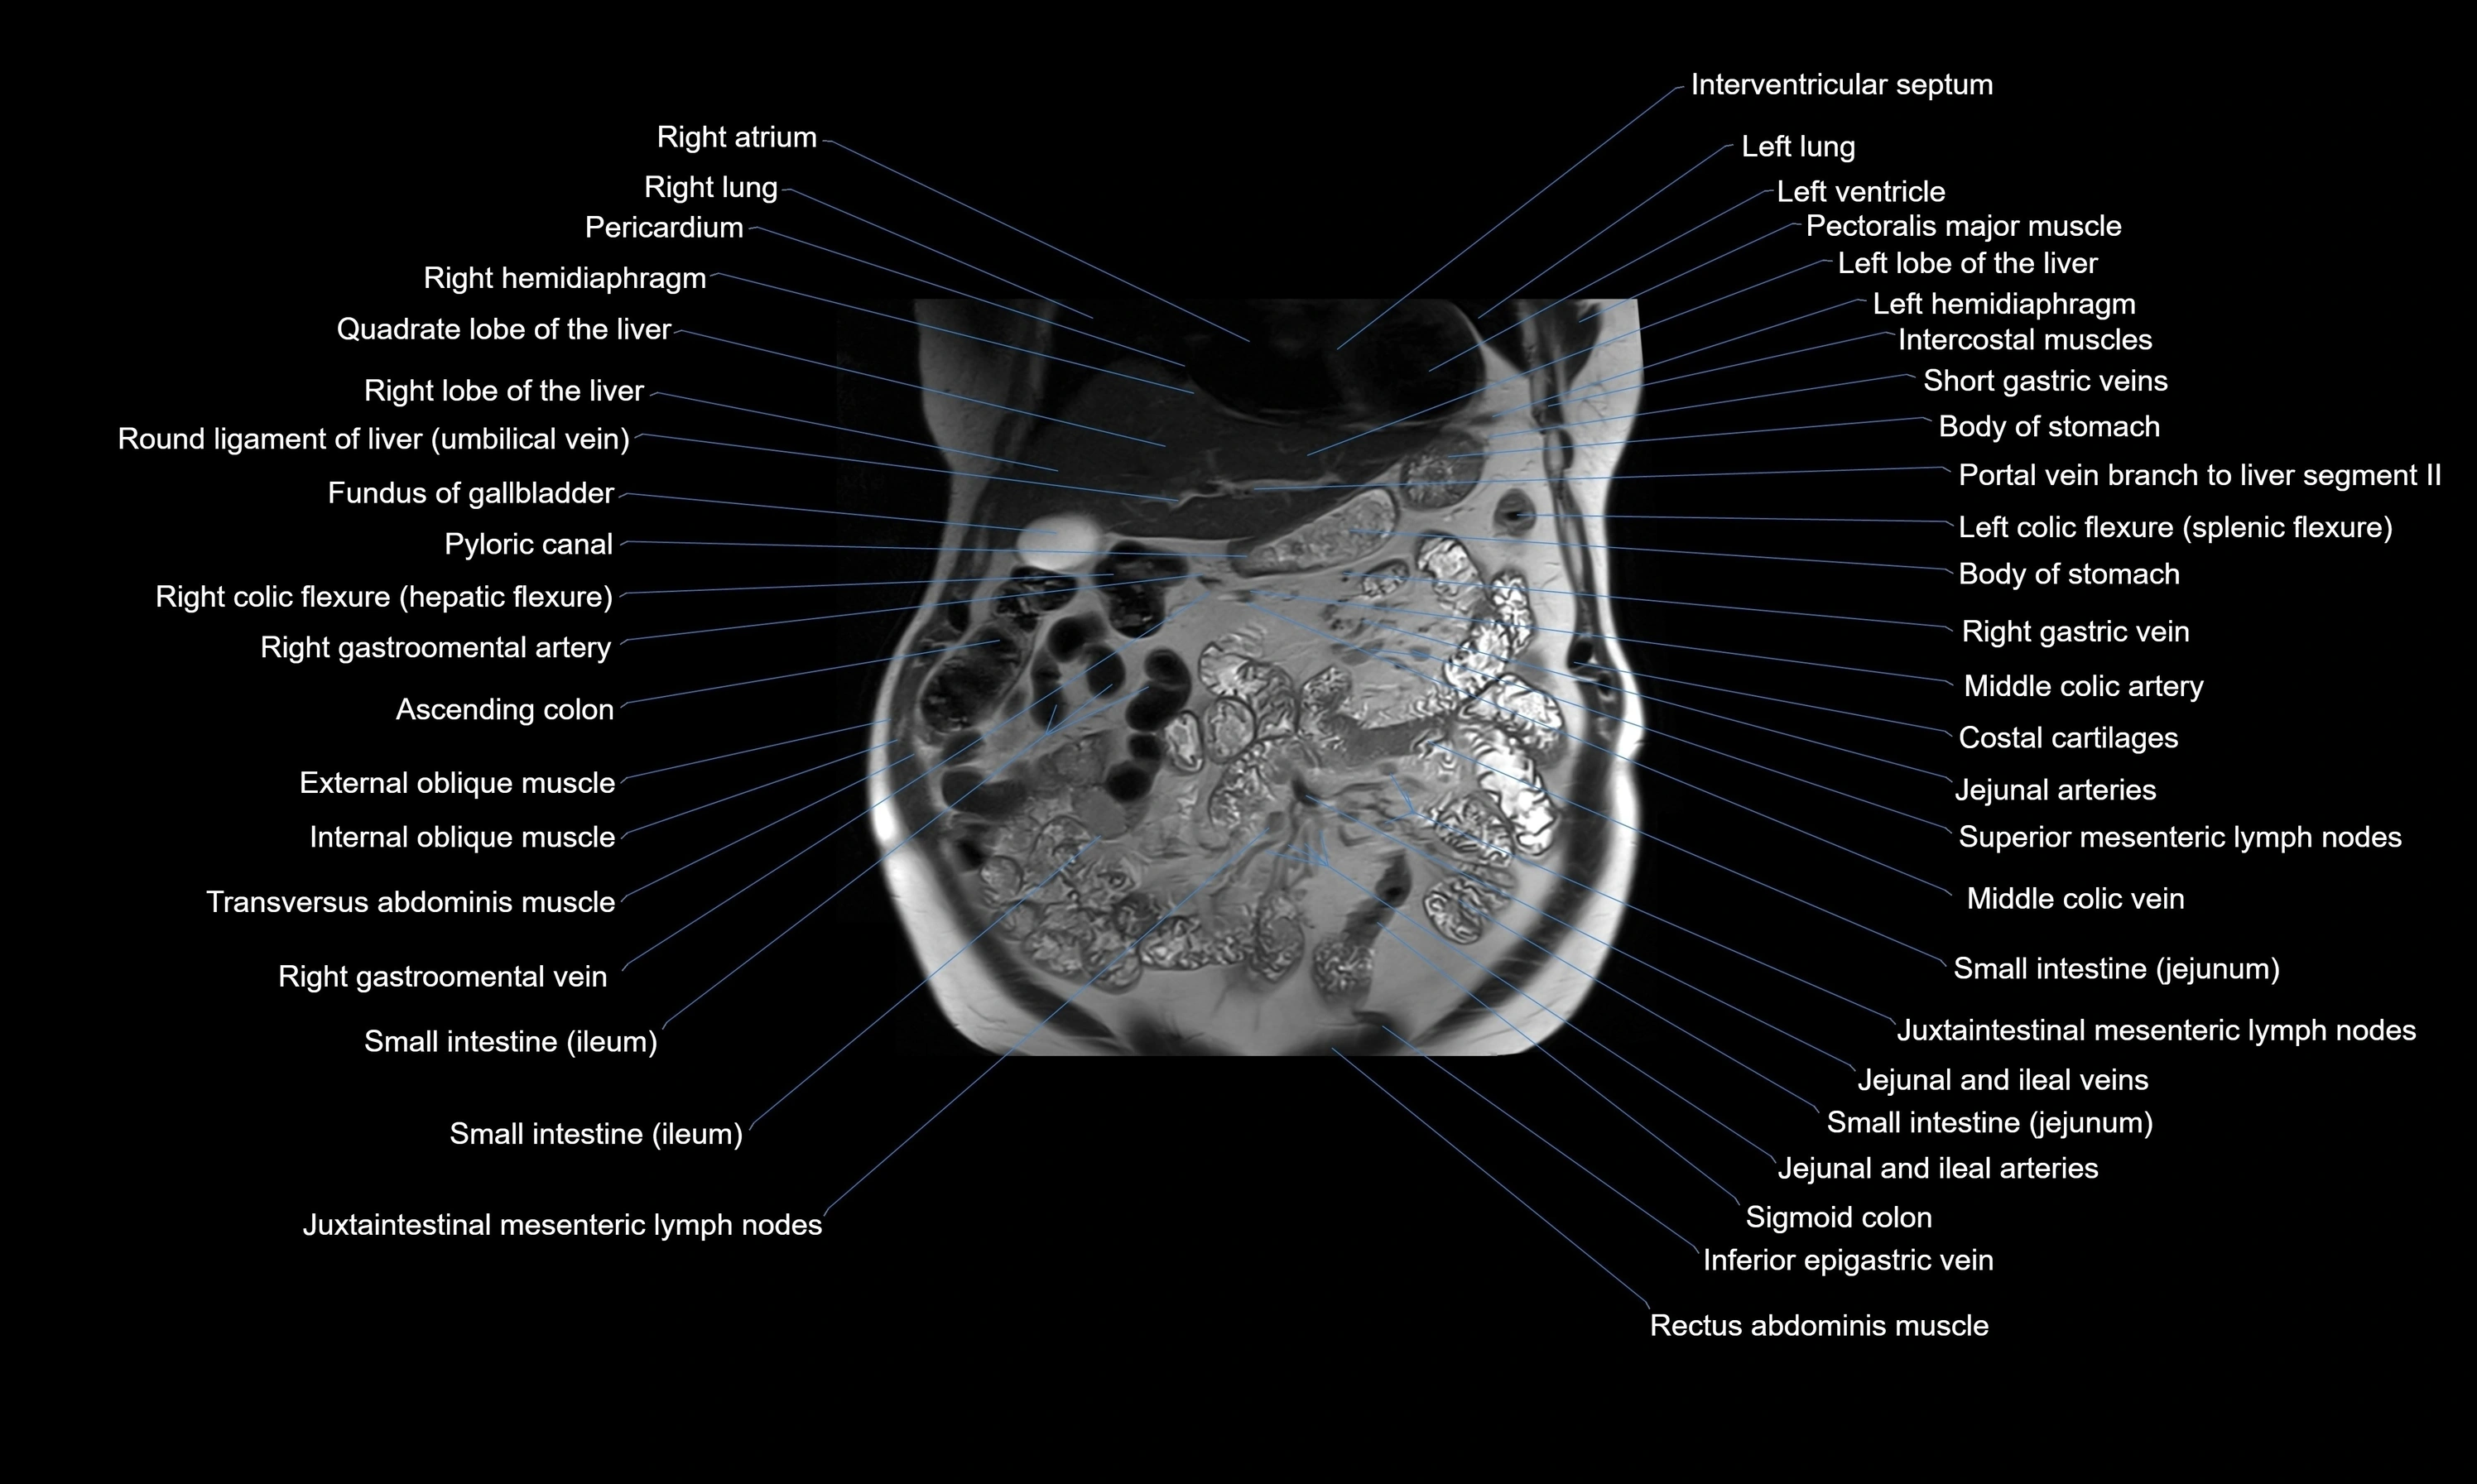

MRI images